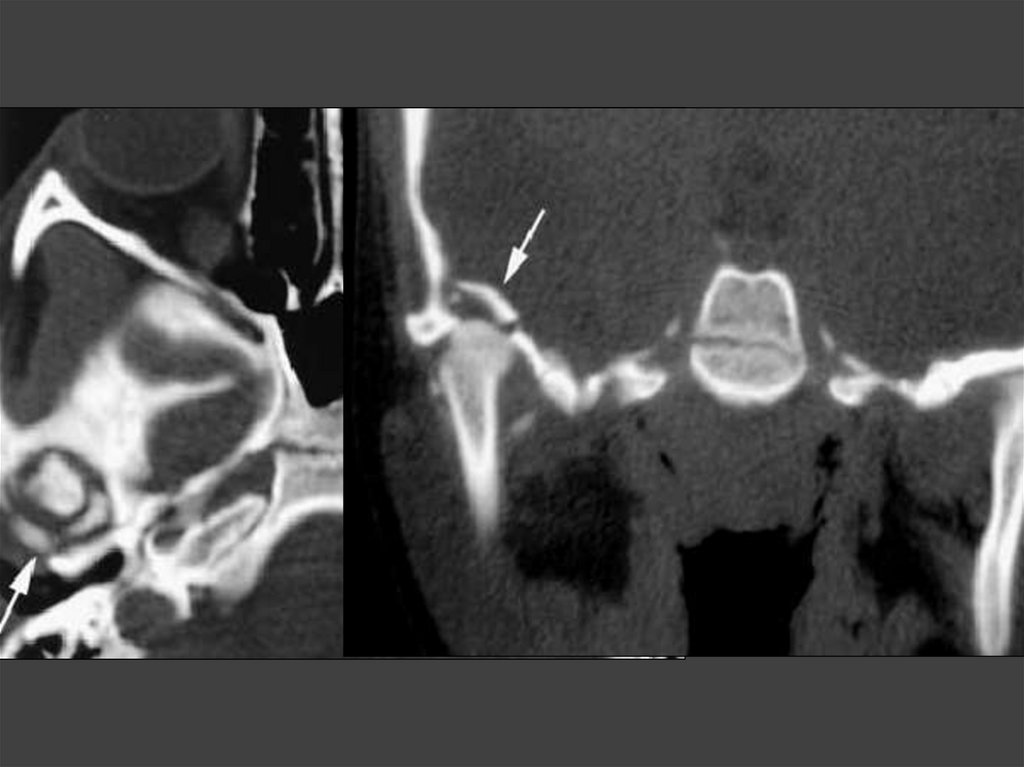

63. Осложнения холестеатомы, выявляемые на КТ

• Фистула лабиринта.

• Разрушение стенок канала лицевого

нерва.

• Распространение холестеатомы на

верхушку пирамиды.

• Внутричерепные осложнения.

66. Холестеатома, разрушение канала лицевого нерва